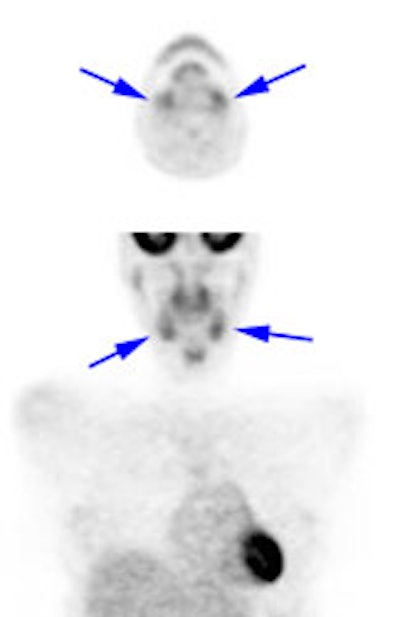

The tonsils are constantly exposed to antigens causing carious

degrees of physiologic inflammation [220]. Low to moderate FDG

uptake occurs in the lingual and palatine tonsils and at the base

of the tongue because of physiologic activity associated with the

lymphatic tissue in Waldeyer's ring [41]. However, tonsil uptake

can be high (SUV 3.11 (lingual) to 3.48 (palatine)) [103],

however, physiologic uptake is typically symmetric and asymmetric

uptake should be regarded as suspicious for malignancy [220].

There is usually uptake in the lymphoid tissue of Waldeyer's ring

[4]. The soft palate can also show tracer uptake [103]. Variable,

but typically low, uptake can be seen in the salivary glands which

secrete low amounts of glucose [41]. The parotids glands also show

mild, symmetric tracer uptake. Due to this physiologic activity,

low grade malignant lesions in the salivary and parotid glands may

be obscured [157]. Additionally, PET imaging is not able to

accurately differentiate benign from malignant parotid lesions as

benign tumors such as pleomorphic adenoma, oncocytoma, and Warthin

tumor are known to be FDG avid [312].

|

Head and neck activity: The images below show typical uptake in the tonsils (black arrows), submandibular glands (blue arrows), and parotid glands (red arrows) |